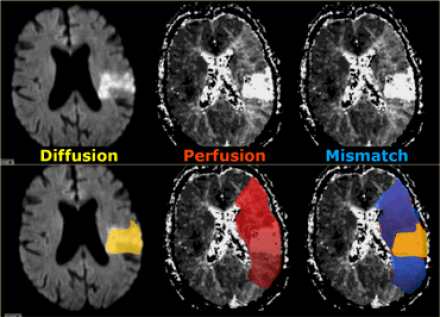

Пенумбра: Окклюзия в СМА. Черным указано ткань с необратимыми изменениями или мертвая ткань. Красным выделена ткань-риска или пенумбра.

При использовании КТ и МРТ-диффузии мы можем с уверенностью найти ту зону, которая ишемизирована, но не сможем сказать о зоне большой ишемической пенумбры (ткань риска).

При помощи перфузии можем ответить на вопрос, какая ткань находится в риске. По статистике 26% пациентам следовало бы выполнить перфузию для уточнения диагноза. Возможности МРТ перфузии и КТ сопоставимы.

Зона с дефектом перфузии является безвозвратно ишемизированной тканью или зоной пенумбры (ткань риска). При комбинировании диффузно-взвешенного изображения и перфузии есть возможность отдифференцировать зоны пенумбры и зоны безвозвратной ишемии.

На нижележащих изображениях слева представлена диффузно-взвешенное изображение, на котором возможно выявить ишемизированную ткань. Среднее изображение соответствует мр- перфузии, на котором визуализируется огромная область гипоперфузии. На крайне правом изображении diffusion-perfusion mismatch визуализируется зона ткани-риска, которая отмечена синим и возможно будет сохранена после терапии.